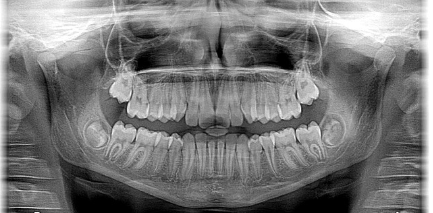

2. 두개골(머리뼈) 방사선 촬영

3. 치아 방사선 촬영